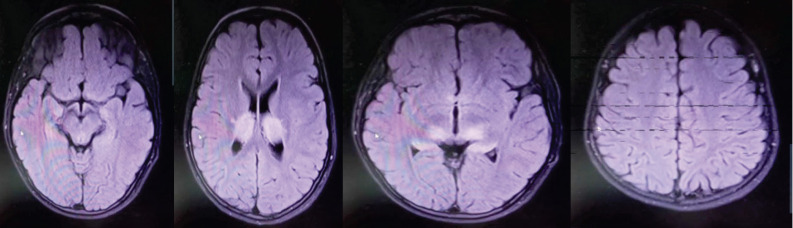

New daily data on the COVID-19 pandemic are circulating globally. This disease usually appears with respiratory symptoms such as cough, shortness of breath, and fever. The neurological complications of the disease are somewhat known in adults but rarely reported in children. Acute necrotizing encephalopathy of childhood (ANEC) is one of the brain complications associated‌ with Coronavirus disease that usually has a poor prognosis in children. In this case, we report a rare case of a 7-year-old boy who was referred to the hospital with symptoms of convulsions after contracting COVID-19 and developed cerebral necrotizing encephalopathy caused by COVID-19 infection. Although ANEC is a rare disease, clinical examination and MRI and CT scan findings play an essentialrole in diagnosing and treating the disease.‌.

Abstract Image